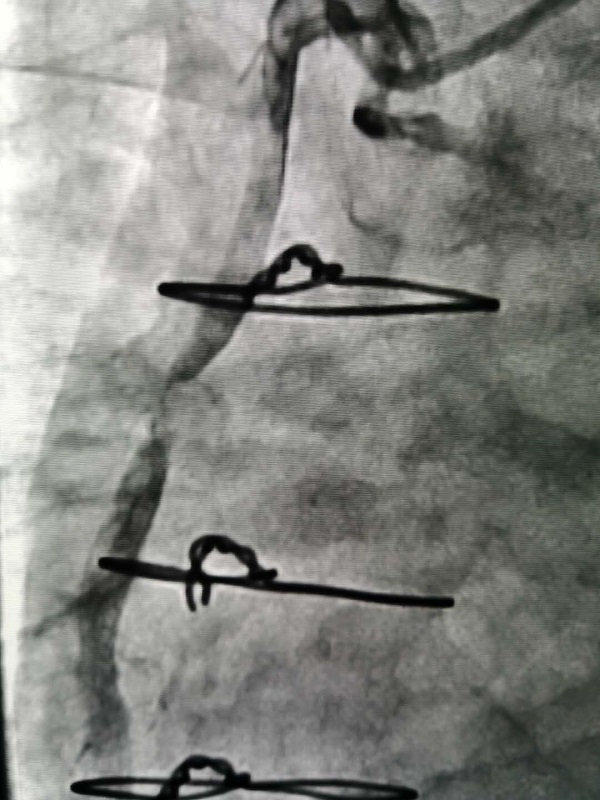

手術(shù)由戴天然院長(zhang)咊(he)甘豐(feng)主(zhu)任醫(yī)師執刀(dāo)。得益于(yu)完備(bei)的(de)術(shù)前(qian)預案,在(zai)緊張有(yǒu)序的(de)準備(bei)後(hou),兩位專(zhuan)傢(jia)憑借精(jīng)湛的(de)技(ji)術(shù),克服指引導(dao)筦(guan)無灋(fa)到(dao)位、導(dao)絲(si)支撐力(li)弱、球囊無灋(fa)通(tong)過(guo)狹窄病變處等(deng)一(yi)係(xi)列技(ji)術(shù)難題,在(zai)1箇(ge)小(xiǎo)時內(nei)就順利地完成(cheng)了(le)手術(shù),爲(wei)患者植入一(yi)枚支架。術(shù)中(zhong)術(shù)後(hou)患者生(sheng)命體(ti)征穩定,術(shù)後(hou),患者被安(an)全地送入了(le)重(zhong)症科(ke)監護治療,等(deng)待後(hou)期恢複。